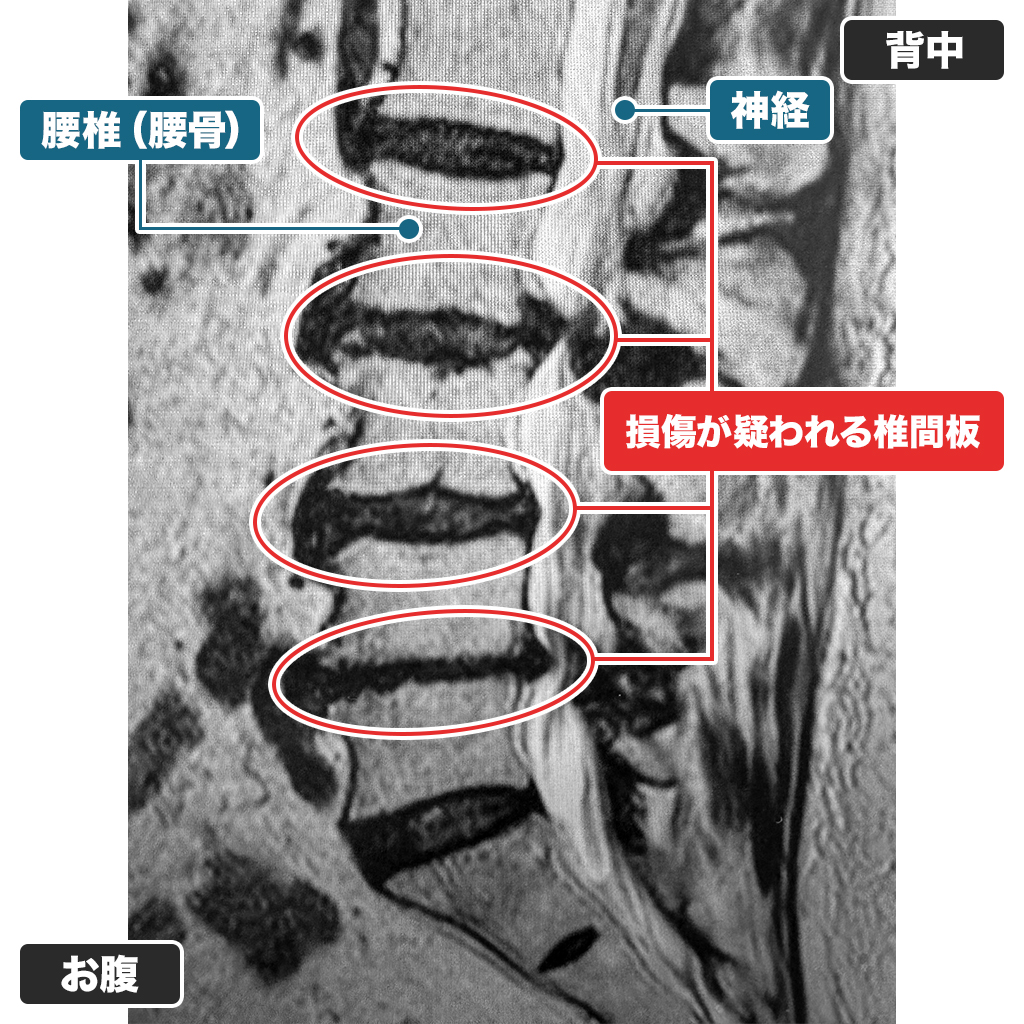

MRI検査

腰のMRI検査では椎間板容量が明らかに減少しており、脊柱管狭窄症の合併を認めます。椎間板容量は50%未満であり、減圧治療(PLDDやディスコゲル治療)は適応外と判断しました。